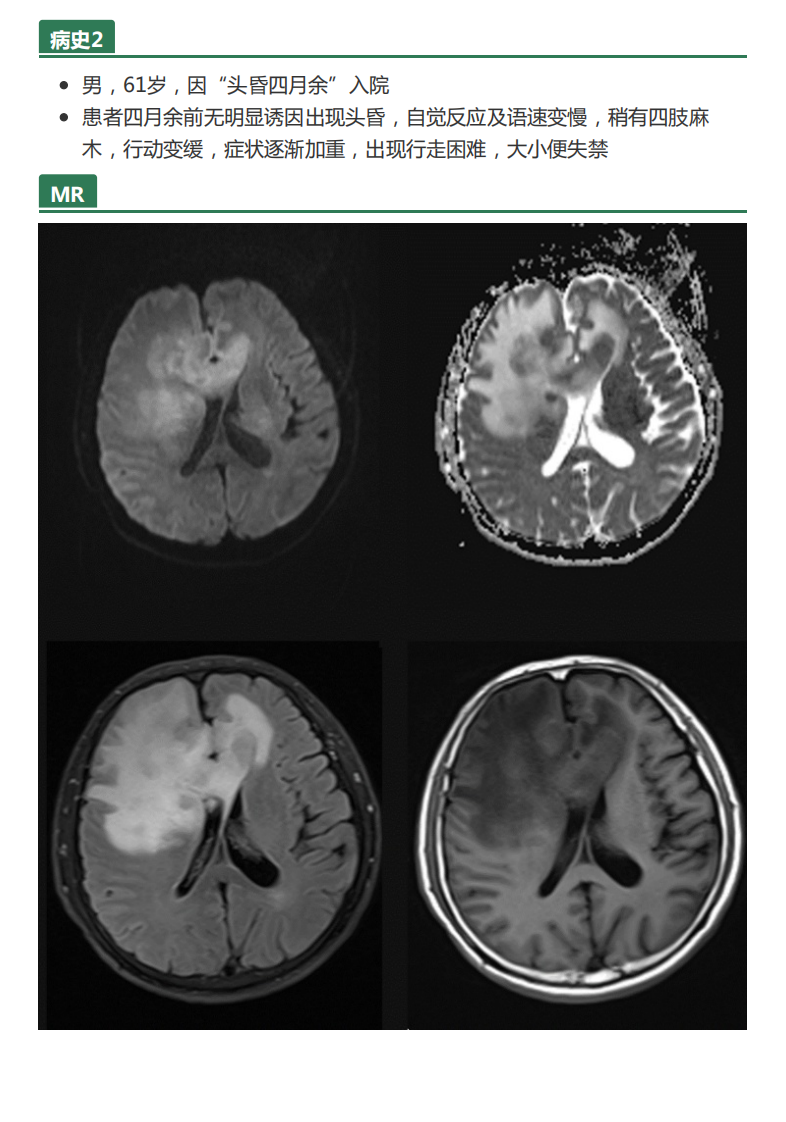

20210608_2【晨读结果公布】2021.06.07神经系统疾病——病例1:间变型少突胶质细胞瘤;病例2:PCNSL;病例3:胼胝体急性梗死.pdf